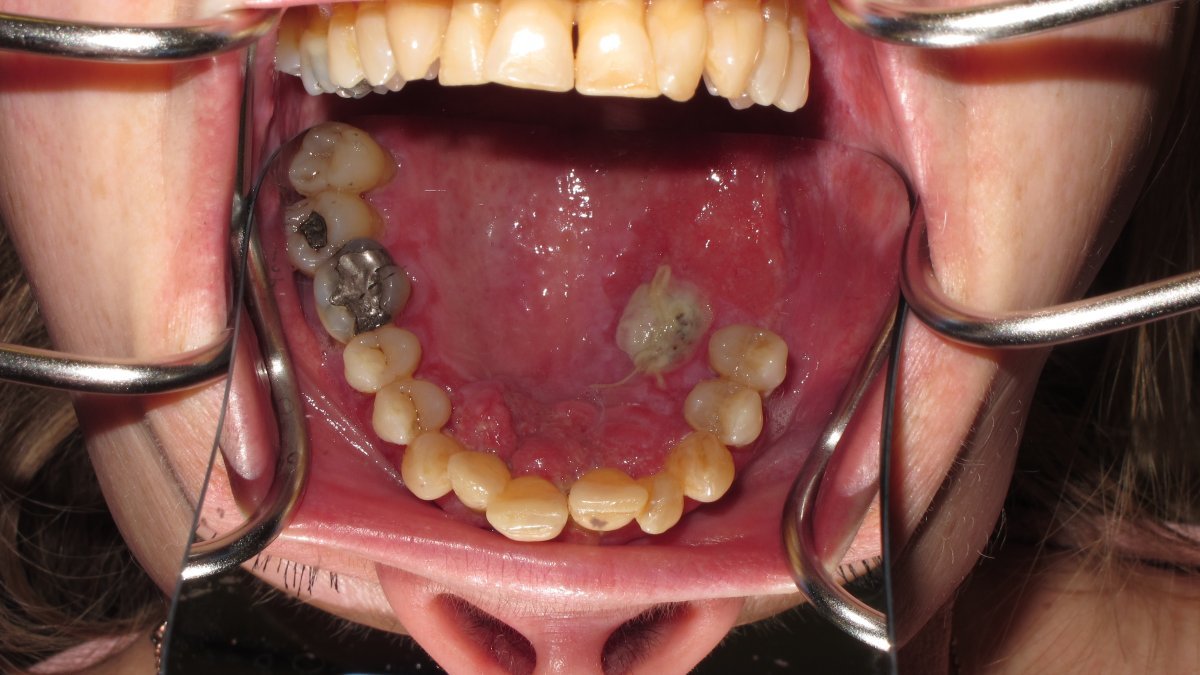

Gingival tumour

Palatal view